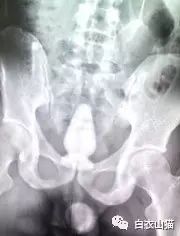

上面是前几年一名患者大肠里的黄鳝。

这条黄鳝还是雌性的黄鳝,你知道我怎么看出来的吗?

医生给他检查的时候,发现已经有腹膜炎症状,怀疑肠梗阻,拍了个片子,就是上面那个片子:一条大黄鳝在肚子里。